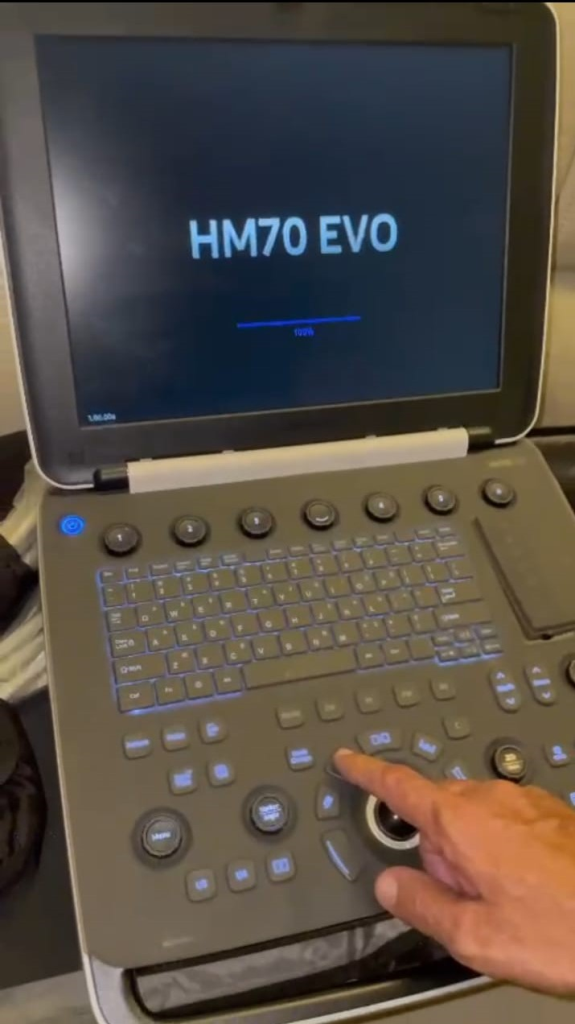

Ultrassom Samsung HM70 EVO com as 3 sondas gerais

- SKU: MI306

- Condição: Semi Novo

- Fabricante: Samsung

* Máquina HM70 EVO********